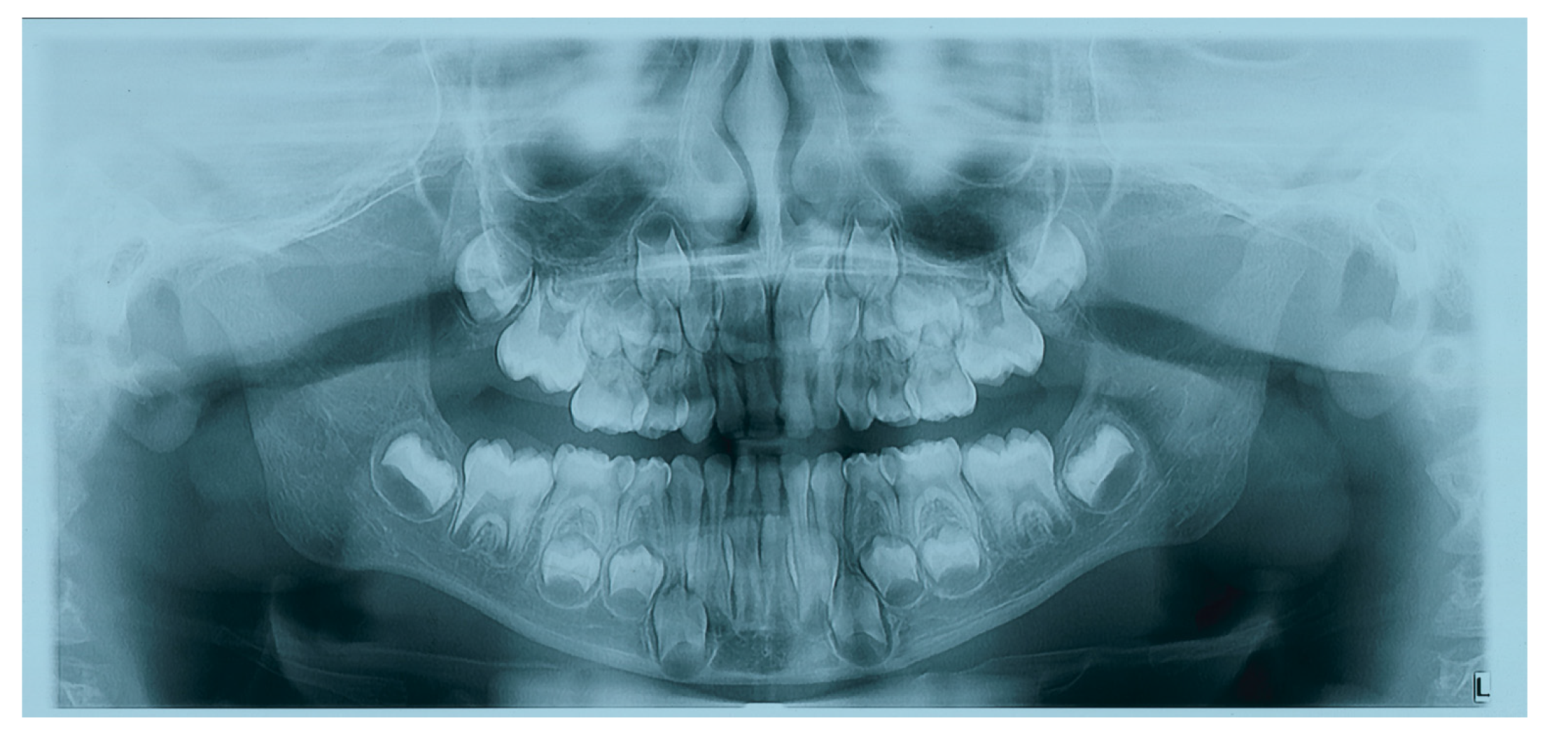

2. Case Report